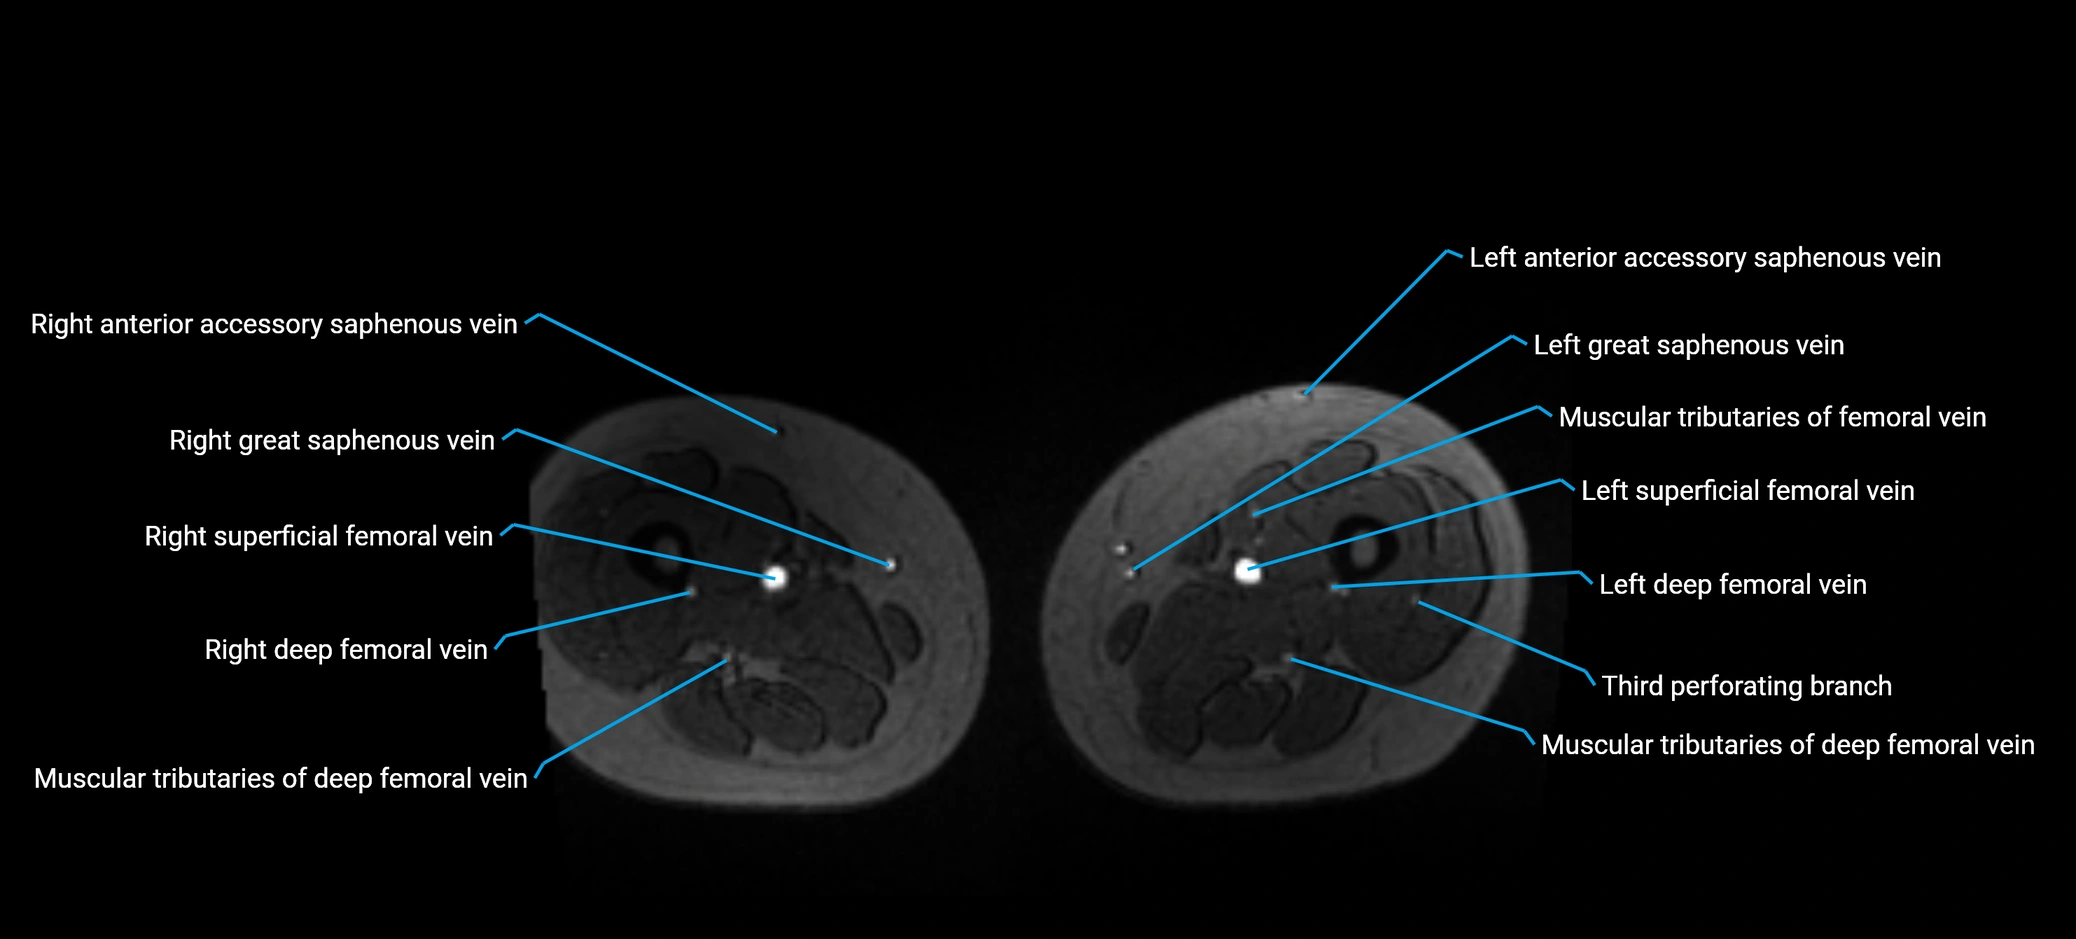

MRI image

image